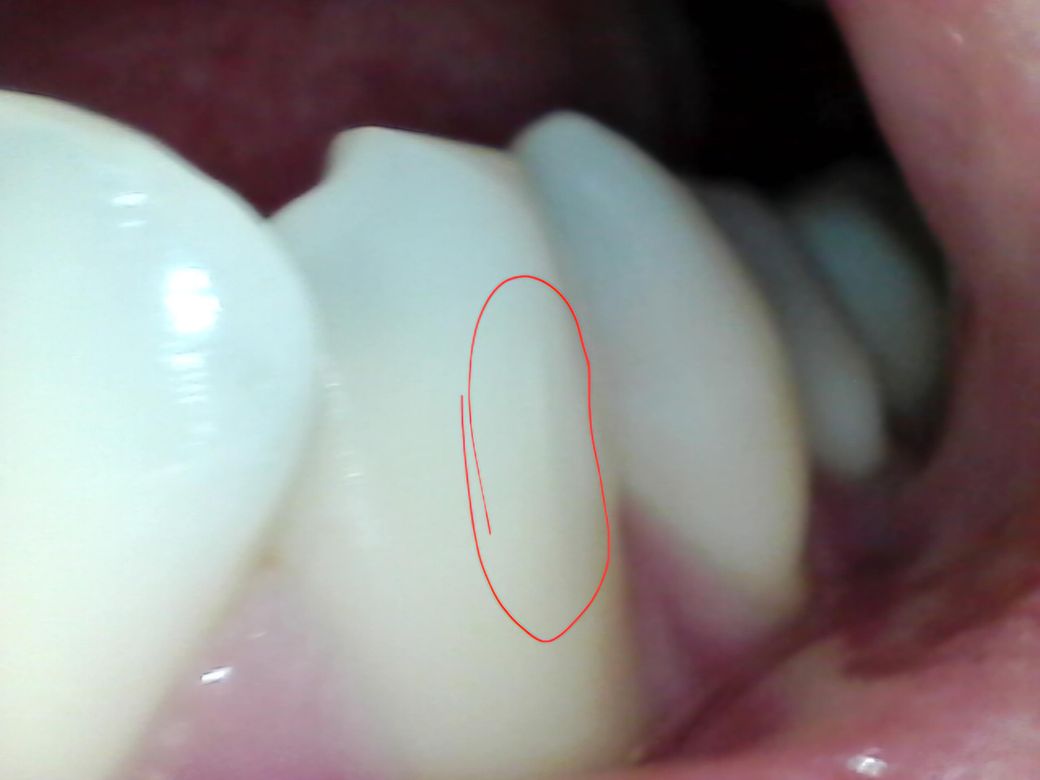

사진에 이 실금 같은거 진짜 치아에 실금이 간건가여???

내시경카메라 같은걸로 입 안에 보는데 불빛 비춰서 보니까 실금같은게 막 다있어여 근데 모든 치아가 이렇진 않은데거의 한 두세개 빼고는 다이렇게 실금같은게 있는데.. 진짜 보이는 그대로 치아에 실금이 가있는건가요?....사진으론 잘 안보이긴 하눈데 실제론 엄청 많아여ㅜㅜ

실금이 갓다고해서 큰 문제가 잇는건 아닙니다. 사진에 보이는 정도는 증상이 없다면 신경쓰지 않으셔도 될것같습니다.

잘 보이진 않지만 실금이 있는 것으로 보이긴 합니다. 증상이 없다면 실금은 따로 치료하진 않습니다.

사진만으로는 실금의 정도를 정확히 확인하기는 어렵습니다. 만약 치아가 시리거나 불편감이 있지 않은 경우에는 문제가 되지는 않으나, 만약 시리거나 통증시에는 신경치료 후 크라운 치료가 필요로 됩니다.

치아에는 미세하게 금이 갈수 있습니다.

사진에 보이는 금은 크게 문제가 되는 금은 아니기 때문에 너무 걱정하지 않아도 될것으로 생각됩니다

하지만 금이 갔다는것은 그만큼 큰 힘이 작용했다는것이기 때문에 치아에 가해지는 힘을 줄이는것이 좋습니다.